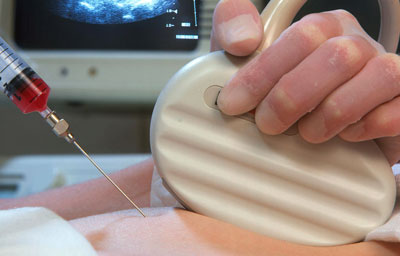

Dr. Ashwini Rathi (MD, MRCOG) is a leading Fetal Medicine Specialist and the Director of Mumbai Fetal Medicine Centre—Mumbai’s first stand-alone dedicated fetal medicine facility. With over 13 years of experience, she is recognized for her precision-driven approach, advanced diagnostic skills, and compassionate care for expectant mothers and their babies.

Advanced Prenatal Procedures Performed

FMF-certified scanning protocols, high-resolution ultrasound, and global screening standards.